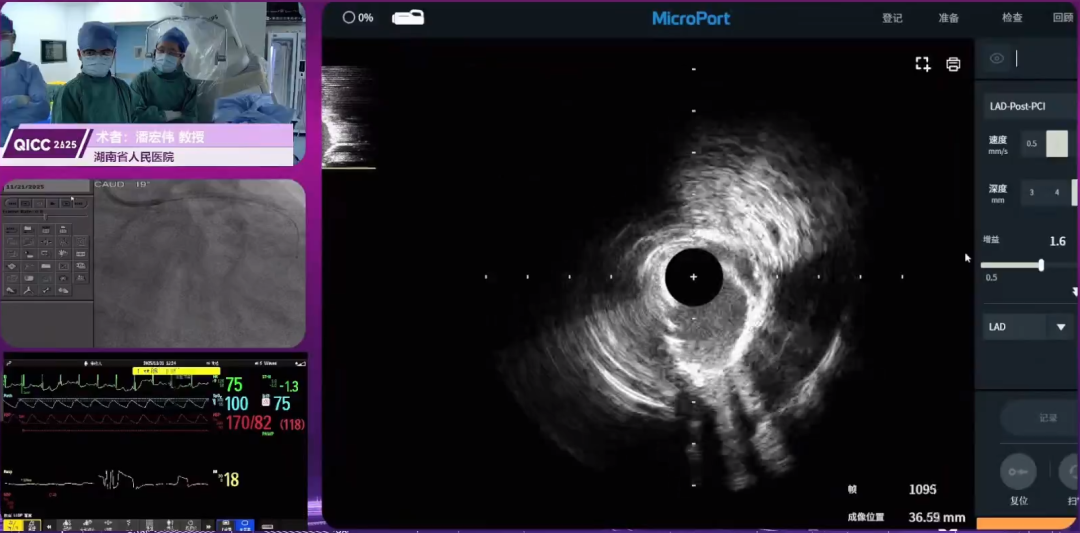

IVUS引导下旋磨联合棘突、冲击波球囊处理左主干-前降支弥漫钙化病变一例

潘宏伟教授演示了一例高龄STEMI女性患者的左主干-前降支弥漫钙化病变处理。冠状动脉造影提示:前降支开口部溃疡病变,近段重度狭窄伴钙化;左主干弥漫性钙化。手术采用双导丝技术辅助开通血管,先顺利将导丝送入回旋支,后续尝试前降支开通时,因前降支开口角度刁钻,导丝到位难度增加,经调整操作后成功建立通路。患者冠脉内血栓负荷较低,先行球囊扩张预处理,术后造影示前降支血流较前改善。进一步使用微创®冠脉Decypher® 天问™血管内超声系统行IVUS检查精准评估:前降支钙化角度大于270°且病变范围弥漫;左主干亦见严重钙化。结合病变特征,术者决定采用FireRaptor®冠脉旋磨系统进一步预处理,遵循 “个体化选择” 原则,选用微创®冠脉1.25mm磨头,以低转速启动旋磨,逐步升速至目标转速,旋磨后予微创®冠脉FireFalcon®棘突球囊扩张修饰病变。复查IVUS提示前降支钙化病变较前改善,钙化环出现 “开环” 表现,但局部钙化负荷仍较重。随后于前降支病变处植入支架,术后即刻IVUS提示支架局部膨胀不全,予球囊后扩张处理,再次复查IVUS仍见局部钙化压迫导致支架贴壁不佳,遂选用3.5mm血管内冲击波球囊进一步行钙化病变碎裂处理,最终实现支架充分膨胀与良好贴壁。